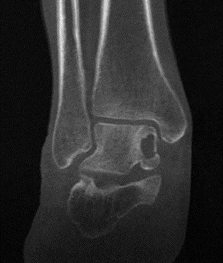

来自山西46岁的樊先生最近过得很痛苦,踝关节疼痛了将近两年,一走路就疼,不能剧烈活动。作为家里的顶梁柱,樊先生却不能久站,不能长时间奔波,工作生活受到了巨大的影响。他一年内辗转多个医院,拍了多次片子,最终确诊为“距骨骨软骨损伤,距骨囊肿(巨大)”。

患者巨大骨囊肿,踝关节面明显受累